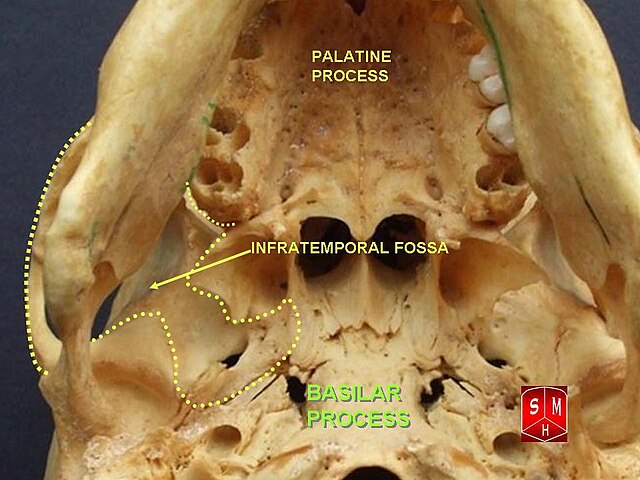

Анатомические особенности: фотографии ямок черепа, височной и подвисочной крылонебной